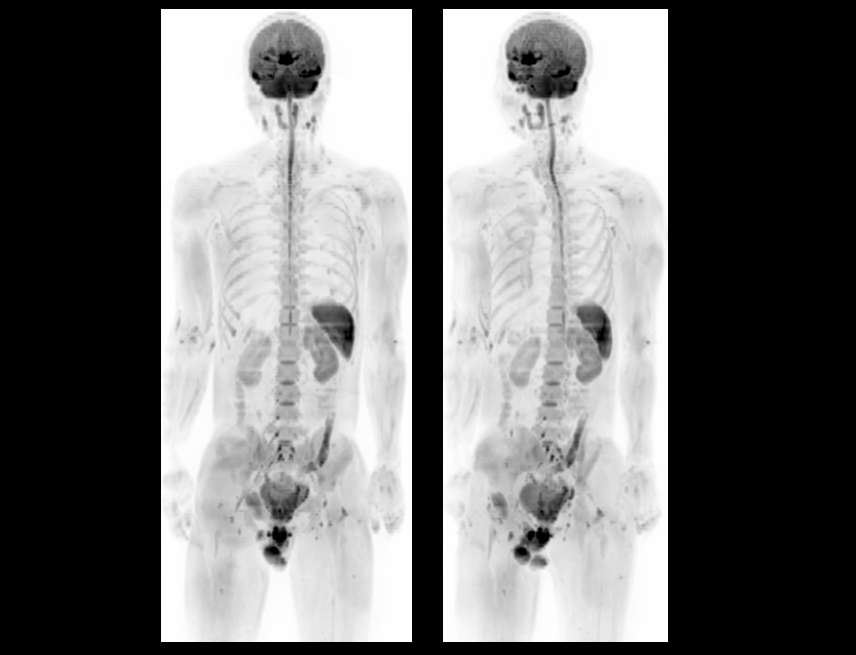

全身弥散 DWI